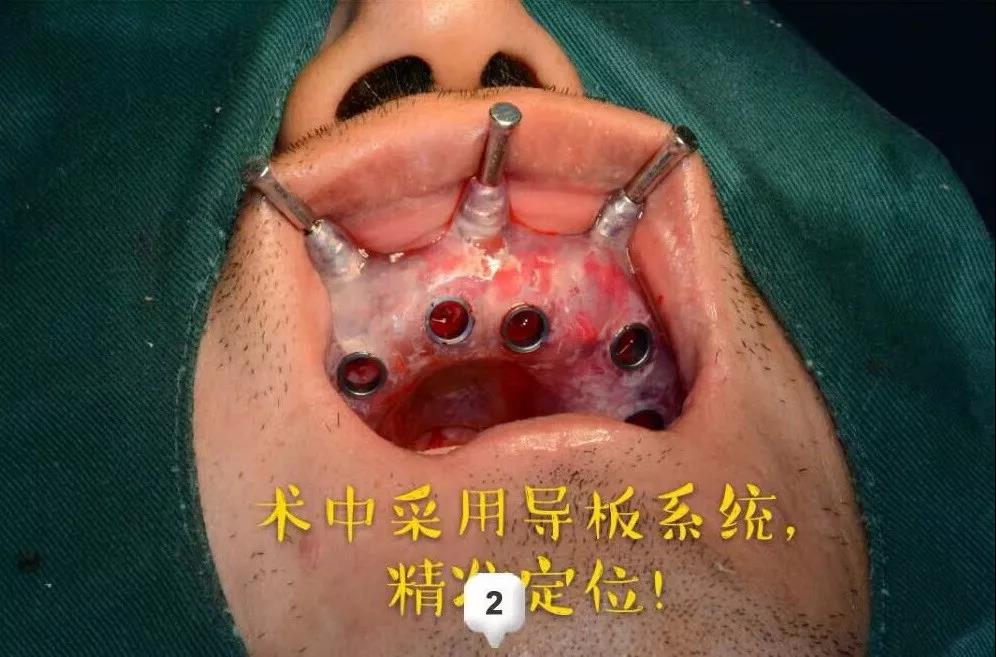

第一次耗时两个多小时:先进行了术前的测量评估,指定手术方案;术中采用数字化种牙导板,精准定位;逐级备洞,植入植体,扭力复合完成植入上半口。